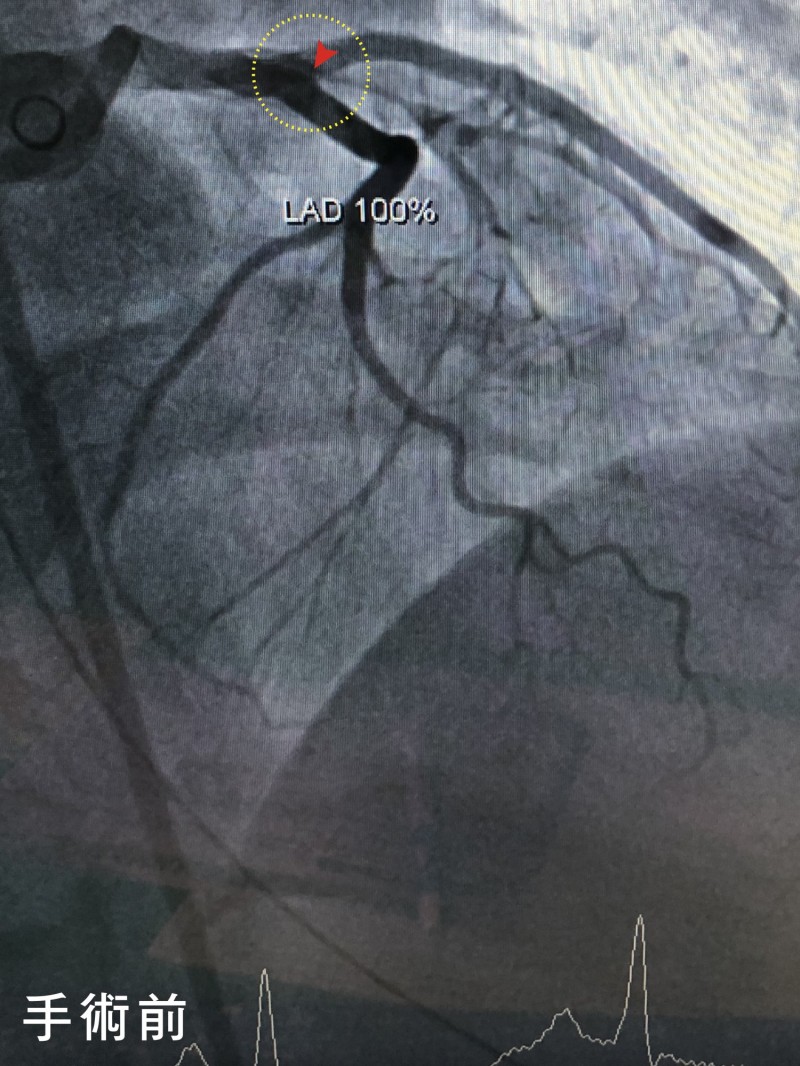

光田醫院重症醫學暨心臟內科醫師柯君樺表示,病人到院檢查發現心臟左前降枝冠狀動脈完全堵塞,右冠狀動脈血栓,經心臟內科醫師黃世忠率領心導管團隊快速搶救在50分鐘內成功完成左前降枝冠狀動脈疏通手術、穩定心血管狀況,續進入低溫治療後逐漸清醒,再經2週治療檢查右冠狀動脈血栓也已消失,未來持續復健、服藥和回診追蹤即可。